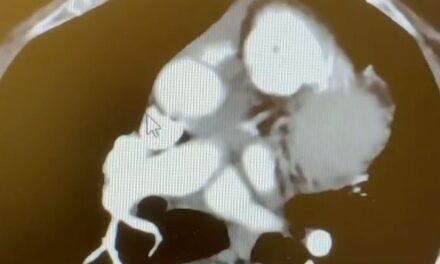

Open Heart Surgery Doesn’t Have to Be Painful

When patients hear they need open heart surgery, the most common reaction is fear, particularly around pain and recovery. The phrase “cracking the chest” has understandably shaped perception, but it does not reflect the modern reality of how thoughtfully a...

Below you can hear testimony from Dennis, a patient of mine, just hours after quadruple bypass surgery! His words are a testament to how advances in techniques allow patients to recover more quickly from open-heart surgery with less pain, fewer complications, and more complete coronary revascularization.